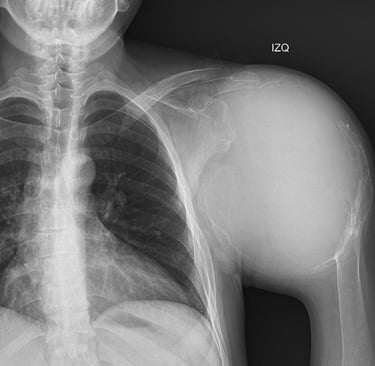

Atención especializada en traumatología y ortopedia para lesiones del sistema musculoesquelético, con alta especialidad en ortopedia oncológica para el manejo de tumores musculoesqueléticos

Conoce acerca de los padecimientos que tratamos, tanto ortopedicos, traumatológicos y ortopedicos oncológicos.

Ofrecemos los tratamientos especializados y personalizados, con enfoque integral multidisciplinario.